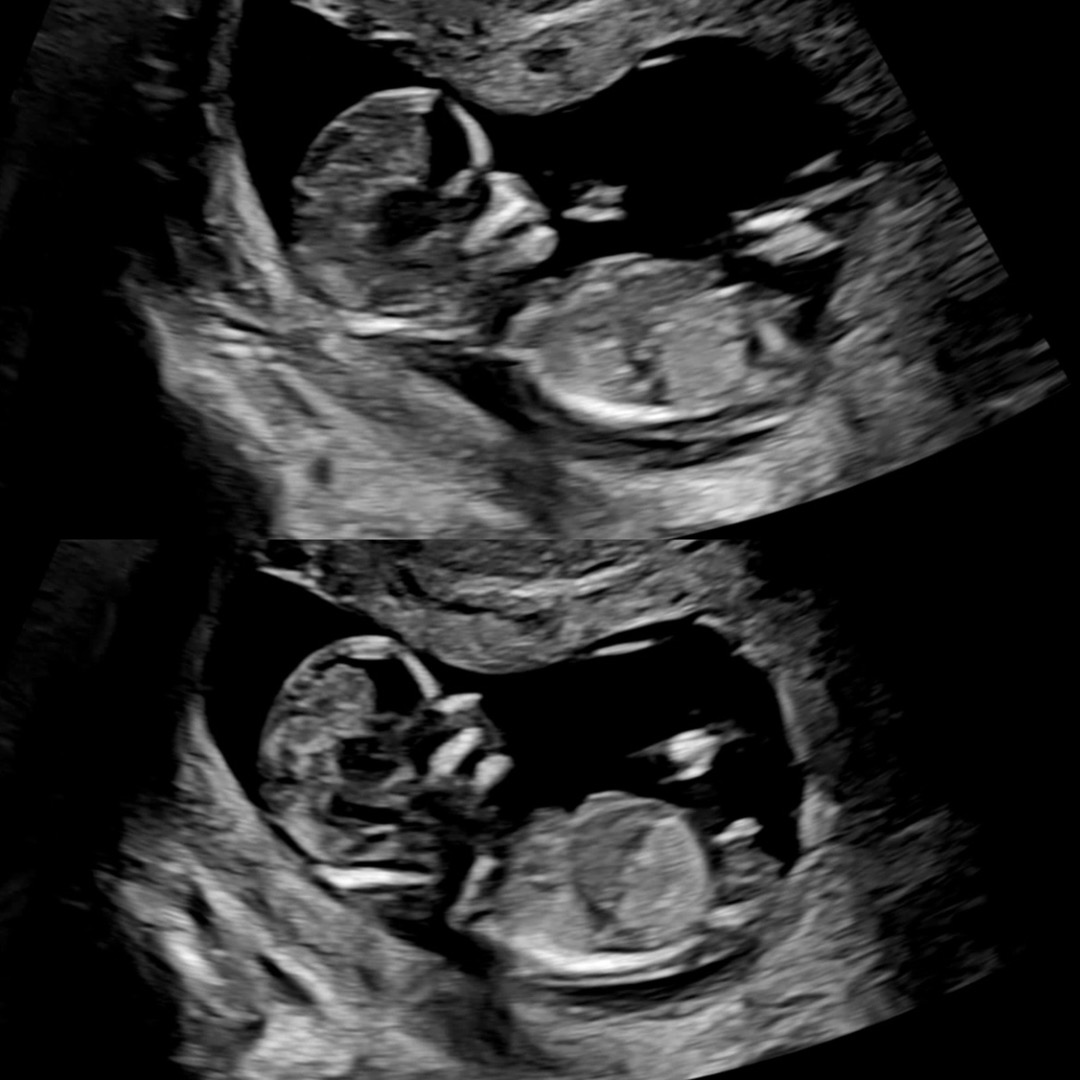

12주4일 각도법 봐주세요~~

각도법 고수님들 한번 봐주세요!! 봐도 모르겠네요 ㅠㅠ

아들 2명같아용